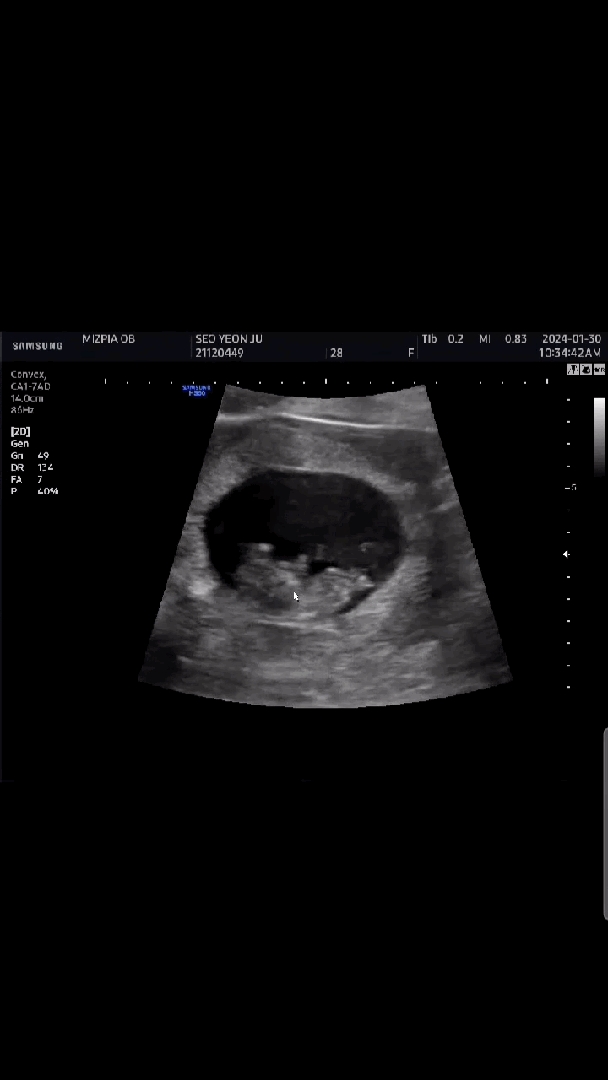

주말내내 코가막히고 목이따끔하더니 결국 코로나 확진받았네요ㅠㅠ 돌아다니지도않았는데 어디서걸린건지 임신하면 면역력떨어진다는 말이 정말 맞나봐요ㅠㅠ 코로나확진받고 약받으러 병원간김에 초음파도 한번더 보고왔는데 혹시나걱정했는데 걱정한게 무색하게 너무 잘놀고있어서 맘이놓였어요 ㅋㅋㅋ 하루종일꼬물꼬물인가봐요 ㅋㅋ 아혹시 이사진으로도 각도법을 볼수있을까요~???